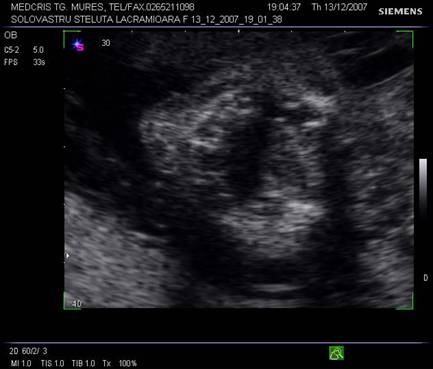

Dupa 13 saptamani in orbita apare si cristalinul in sectiunea parasagitala.

Fig. nr. 160 . Cristalinul hiperecogen, rotund in orbita dreapta .